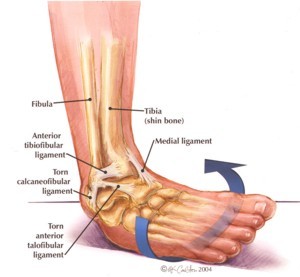

When there is a lateral ankle sprain, which ligaments are affected?

1. Anterior/posterior talofibular ligaments

2. Calcaneofibular ligaments

1. Pain

2. Bruising

3. Mild/moderate tenderness